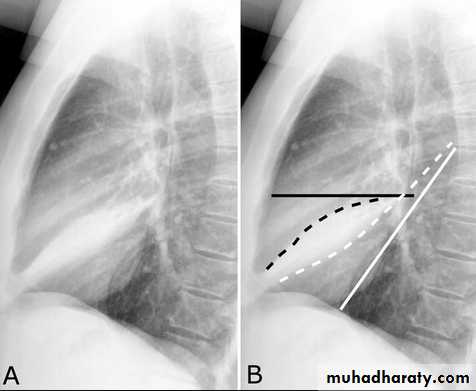

Pleural Effusion on Chest Radiographs.

Posteroanterior (A) and lateral (B) chest radiographs demonstrate the typical meniscoid appearance (arrows) in a patient with a left pleural effusionHydropneumothorax.